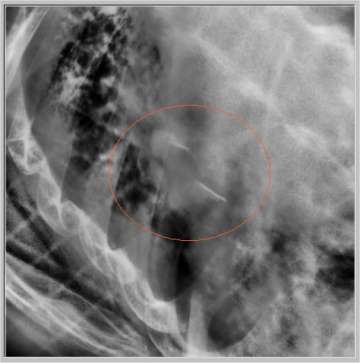

Stereotactic Body Radiation Therapy (SBRT) is a treatment procedure similar to central nervous system (CNS) stereotactic radiosurgery, except that it deals with tumors outside of the CNS. A stereotactic radiation treatment for the body means that a specially designed coordinate-system is used for the exact localization of the tumors in the body (Figure 1) in order to treat it with limited but highly precise treatment fields. SBRT involves the delivery of a single high dose radiation treatment or a few fractionated radiation treatments (usually up to 5 treatments). A high potent biological dose of radiation is delivered to the tumor, improving the cure rates for the tumor, in a manner previously not achievable by standard conventional radiation therapy (Figure 2).